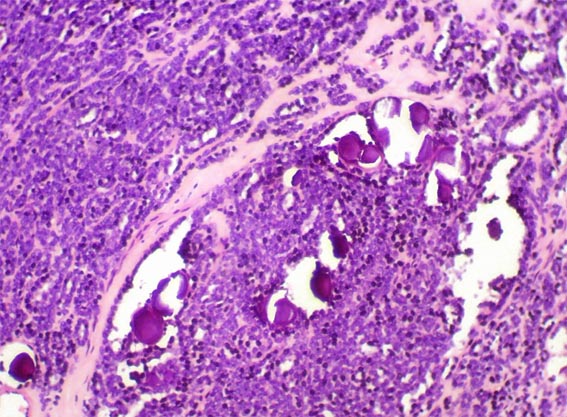

Figura 4.

H&E, X100.